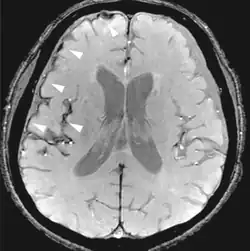

| Susceptibility-weighted | SWI | Spoiled gradient recalled echo (GRE), fully flow compensated, long echo time, combines phase image with magnitude image[12] | Detecting small amounts of hemorrhage (diffuse axonal injury pictured) or calcium.[12] |

| Fluid-attenuated inversion recovery | FLAIR | Fluid suppression by setting an inversion time that nulls fluids | High signal in lacunar infarction, multiple sclerosis (MS) plaques, subarachnoid haemorrhage and meningitis (pictured).[15] |

| Double inversion recovery | DIR | Simultaneous suppression of cerebrospinal fluid and white matter by two inversion times.[16] | High signal of multiple sclerosis plaques (pictured).[16] |

Susceptibility weighted imaging

Susceptibility-weighted imaging (SWI) is a new type of contrast in MRI different from spin density, T1, or T2 imaging. This method exploits the susceptibility differences between tissues and uses a fully velocity-compensated, three-dimensional, RF-spoiled, high-resolution, 3D-gradient echo scan. This special data acquisition and image processing produces an enhanced contrast magnitude image very sensitive to venous blood, hemorrhage and iron storage. It is used to enhance the detection and diagnosis of tumors, vascular and neurovascular diseases (stroke and hemorrhage), multiple sclerosis,[52] Alzheimer's, and also detects traumatic brain injuries that may not be diagnosed using other methods.[53]